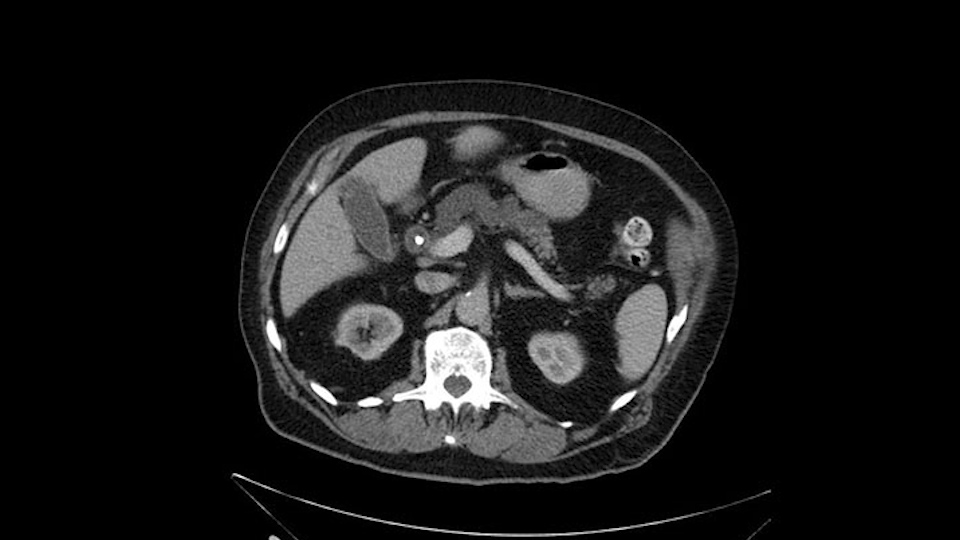

He has no liver metastases or obvious metastatic disease. On reviewing his CT scan, he has normal vascular anatomy; he has no involvement of the portal vein by the looks of it, or the superior mesenteric vein.

The only difference with him is that he has fairly extensive cystic lesions throughout his pancreas, particularly in the head and the neck. We have thought how this might affect the procedure. Likely IPMN (Intraductal Papillary Mucinous Neoplasms), and we have thought how this might affect the procedure. Is this a pancreatic adenocarcinoma rather than an ampullary cancer? The ampulla (of Vater) was abnormal on a side-viewing scope and a biopsy of this ampulla was adenocarcinoma. So I don’t think this was just a mass invading into the duodenum.

Number two, the reason why I think this IPMN might affect the procedure: it is involving the neck. So normally when we come across the neck, we would like to see a normal pancreas with a small or a large duct but you can see on the scan that this is fairly extensive duct and cystic lesion at that point. The only slowing down moment for me is really that. Coming across the pancreas, then wanting to see what that looks like and how that is going to affect my anastomosis.

Anyhow. What the surgeon does need to do though, is focus on the resection. What I generally do is look at the tumor, which is here, and then I look at the nature of the pancreas. That’s really just to get an idea on what it would be like to do the pancreatic anastomosis, which isn’t technically the biggest deal, but it’s the biggest deal for the patient afterwards; and the larger the duct and the harder the pancreas, the less likely it’s going to leak. Leaks are what cause almost all the morbidity so I do think of it mentally. I wouldn’t do anything differently, the night before or the morning or the surgery or during the surgery, but certainly mentally it’s useful to know that you may have a challenge in terms of doing the best pancreatic anastomosis you can. I think the duct is quite large. The interesting thing about the duct: it does peter out into fairly normal looking pancreas; that’s a bit strange. But I’ll assume the duct is large.

The next item that I would look at: the issue would be the vessels and usually start at the portal vein, watch the portal vein, follow it down, down-down-down to the neck of the pancreas - which is here - and there’s no impingement by tumor, which is great. The SMV and the splenic vein, which is here. The splenic vein junction is normal, which is great.

The other thing I look at is the gastroepeiploic arcade- which is this thing here- which is where the gastroepeiploic vein joins the portal vein. I call it the gateway to the neck of the pancreas because you pretty much have to divide it to get to the neck. The middle colic vein usually drains either into it or nearby. I think we’re seeing it here. Again,that can be divided and I usually divide those two and it helps me get under the neck. Again, there’s no issues here with the tumor so it’s nice from that perspective. If I was concerned about the vein, which I’m not here, I would go to the coronal view. It’s a nice way to look at the vein on just a couple of cuts and you can see a beautiful view of it here. There’s the portal vein, there’s the head of the pancreas. There’s the tumor. It’s a little closer here than it looks on the other one. I doubt it’s involved. If it’s touching, it may not be invading it but even if it was, it's a short segment. Anyways, there’s the SMV there’s the splenic vein, and everything looks good. You can see the stent. I ignore the stent. It’s the most dramatic looking thing in the picture but it’s actually the least important.